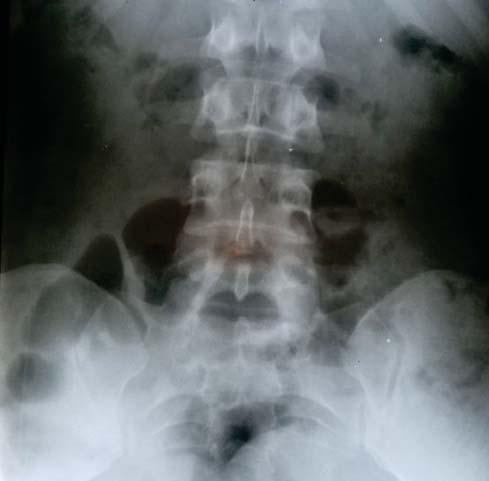

ACCIDENTE DE TRÁNSITO DEJÓ UNA SECUELA ‘IRREVERSIBLE’ EN MÍ”

El peor momento de mi vida sucedió cuando sufrí un accidente, que causó graves daños irreversibles en mi columna vertebral. Esto me provocaba intensos dolores que me impedían estar sentada. De esa manera estuve

viviendo por dos años con fuertes dolores. Iba a las terapias, pero nada funcionaba. Me encontraba deprimida y sin rumbo hasta que me invitaron a participar en la iglesia Universal. Perseverando los martes por mi sanidad, logré revertir ese diagnóstico.

y dos as

Además, poco a poco, empecé a entregar mi vida a Dios y a usar mi fe para poder ver lo Sobrenatural en mi vida. Hoy estoy completamente sanada.

Juliana Rodríguez Juuliana